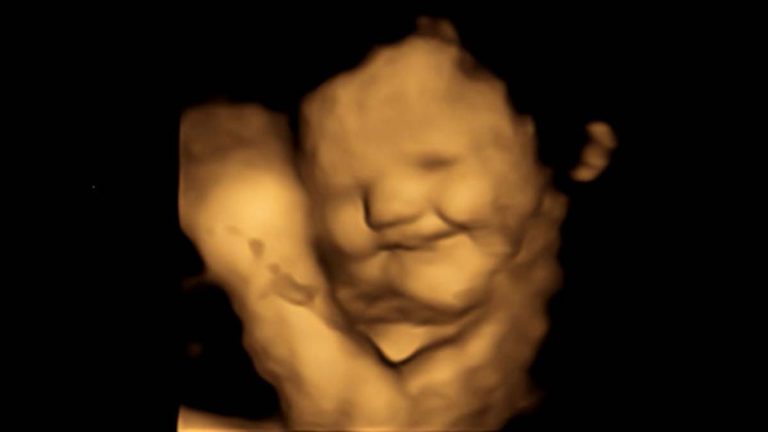

Bebés identifican sabores de alimentos desde el útero según un estudio